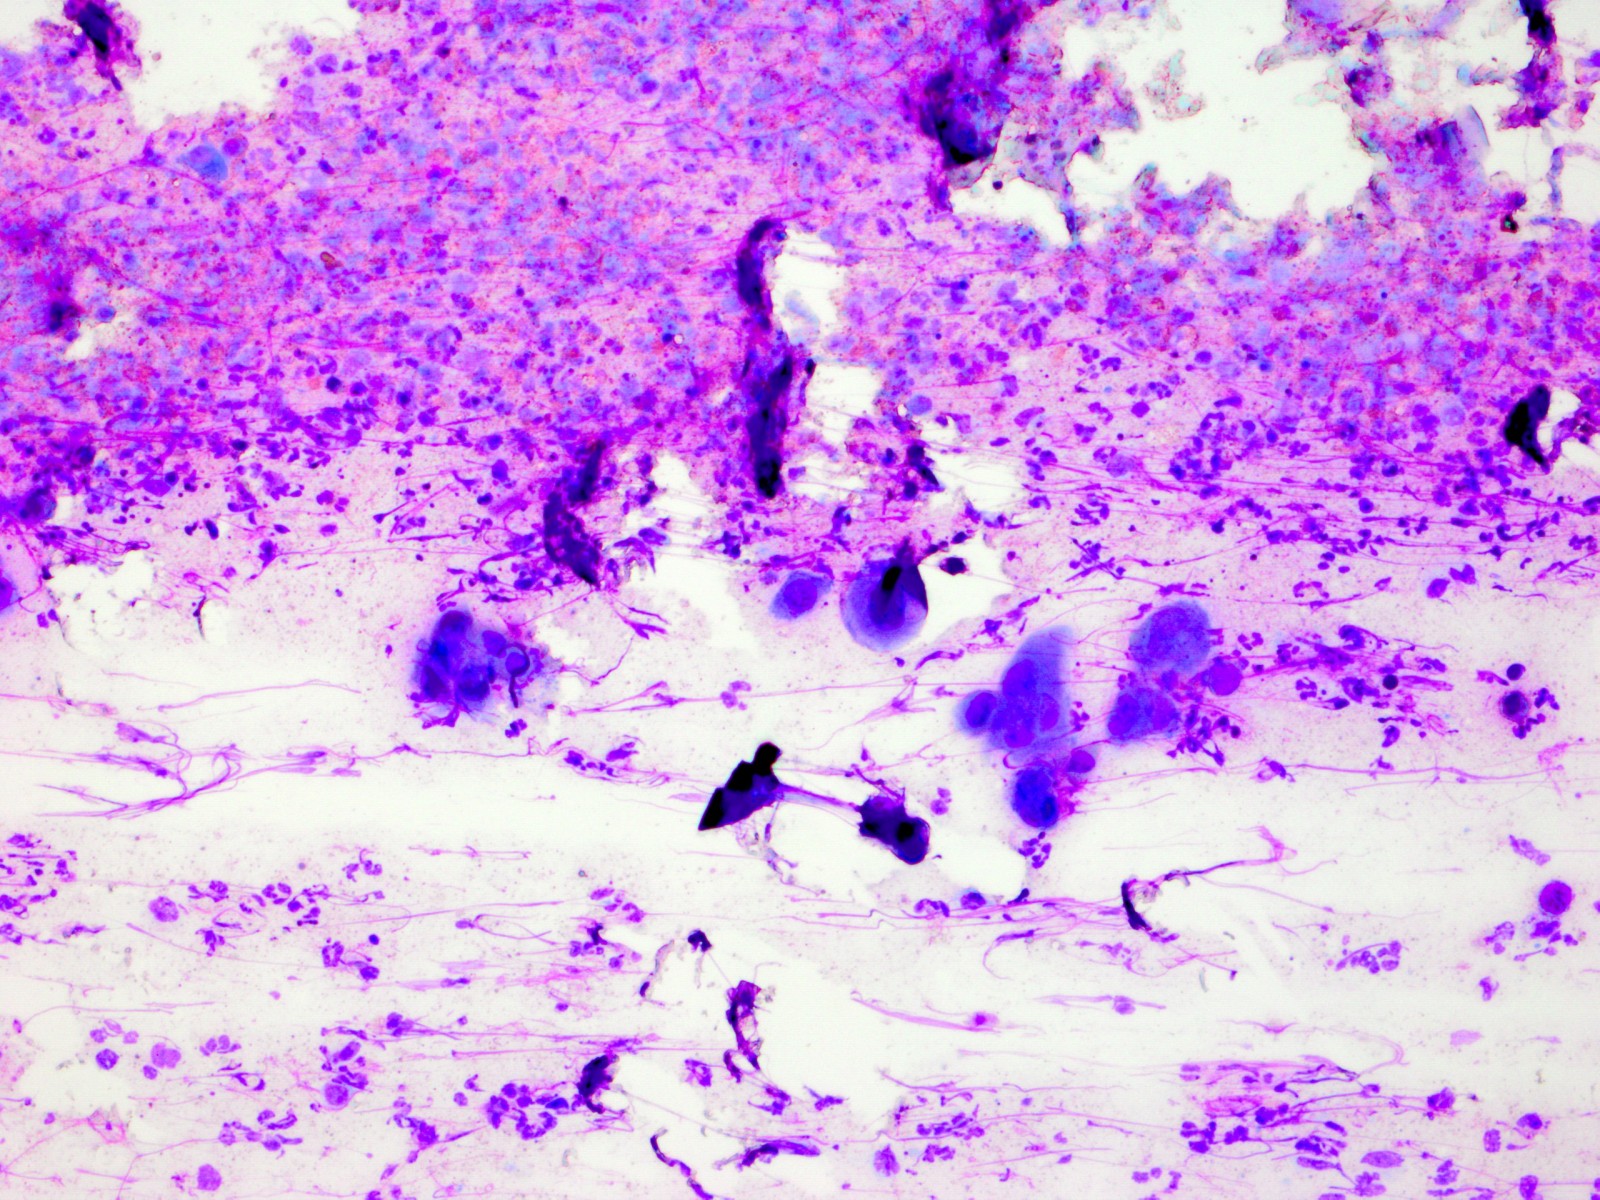

De Tzanck reuscellen hebben in het Diff-Quick preparaat een lichtblauw (basofiel)

cytoplasma en een homogene donkerblauwe of paarse kern (hyperchromatisch, sterk

aankleurend), en zijn zeer groot, veel groter dan een granulocyt. Het zijn geen

macrofagen of Langhanse reuscellen, het zijn conglomeraten van grote epitheliale

cellen (keratinocyten). Er kunnen in het preparaat ook losse van deze grote

hyperchromatische epitheelcellen liggen, maar diagnostisch is het vinden van

een klompje waarbij het cytoplasma samengesmolten is en de kernen tegen elkaar

aanliggen. Losliggende grote afgeronde epitheelcellen (Tzanck cells) kunnen

![Tzanck test met multinucleate giant cells (click on photo to enlarge) [source: www.huidziekten.nl] Tzanck test met multinucleate giant cells](../../../images/soa/Tzanck-test-3z.jpg) |

| Tzanck

test |